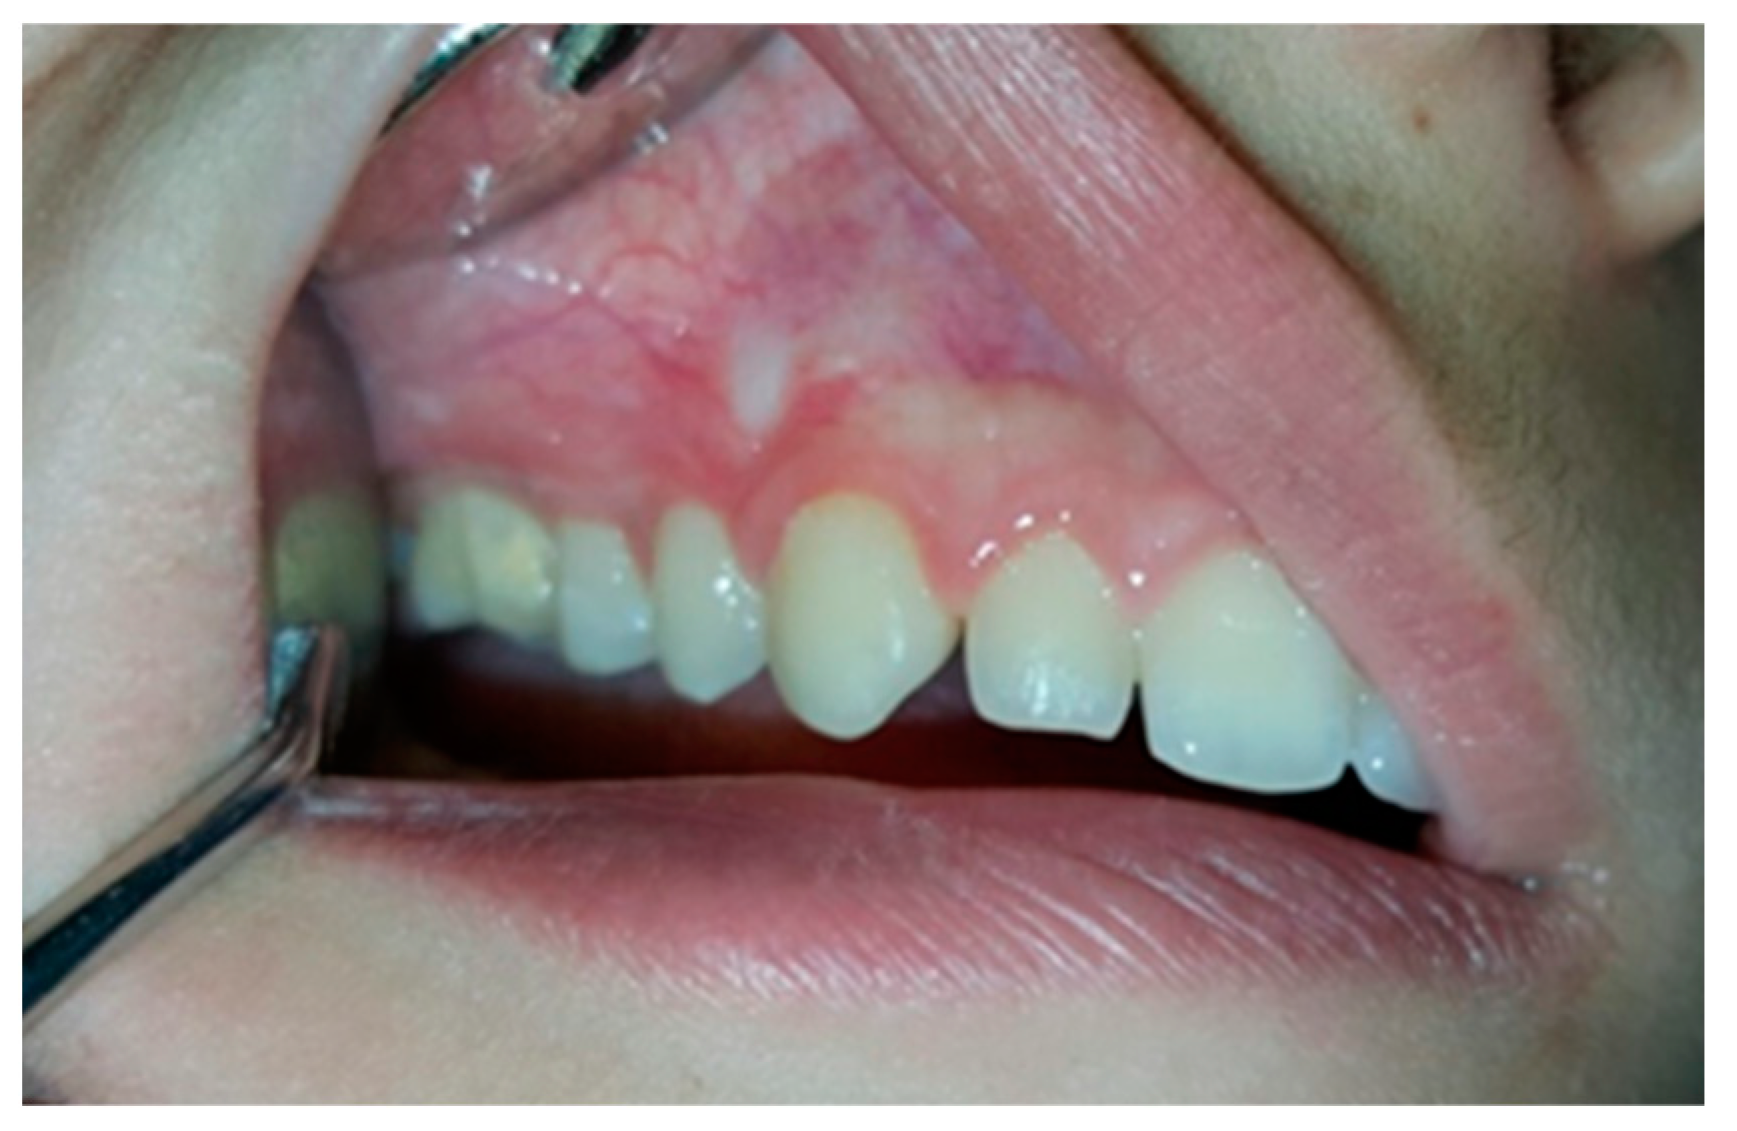

2. Case Presentation